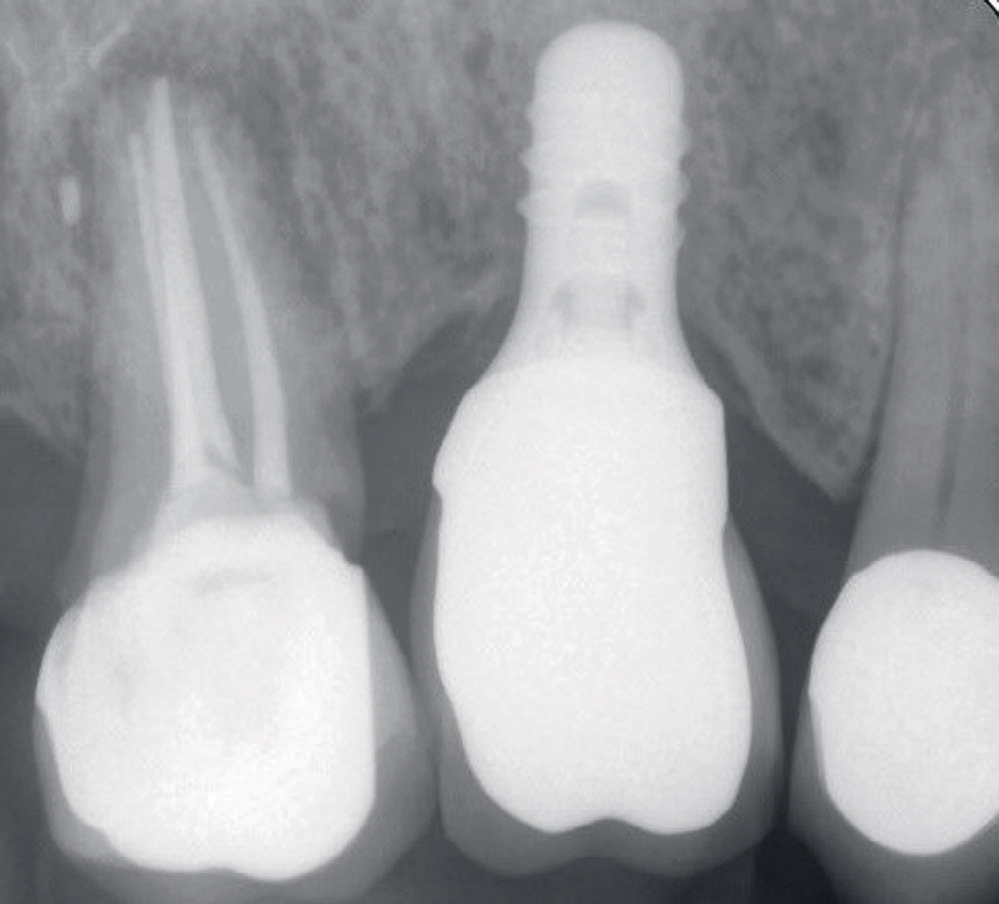

Status presens: ved ekstraoral undersøkelse av hode-/halsregion, kjeveledd og tyggemuskulatur ble det påviste stram tyggemuskulatur; ellers ingen anmerkning. Intraoral undersøkelse viste et velkonservert tannsett, god munnhygiene, men tydelig okklusal slitasje på tenner/kronerestaureringer. Pasienten informerte om tanngnissing. Mobilitet ble diagnostisert i bukko-palatinal retning på implantatkrone regio 16. Kronen hadde en voluminøs utforming og okklusalt var det tydelige slitasjeskader i porselenet særlig i det mesio-palatinale cuspområdet (figur 1). Det var ikke mulig å måle lommer eller blødning rundt implantatet. Røntgen 1. kvadrant viste tannretinerte kroner 17,15 og implantatstøttet krone regio 16. Endodontisk behandlet 17 viste apikal forandring, overskudd av rotfyllingsmateriale og sekundær karies i kronekanten mesialt, som henvisende tannlege har valgt å observere. Implantat regio 16 manglet benkontakt langs hele implantatets lengde (figur 2 og 3).

Figur 2. Røntgenbilde fra april 2018 før fjerning av kronen viser endret benmorfologi langs hele implantatets lengde.

Figur 3. Røntgenbilde fra april 2018 etter fjerning av kronen dokumenterer også endret benmorfologi langs implantatet.